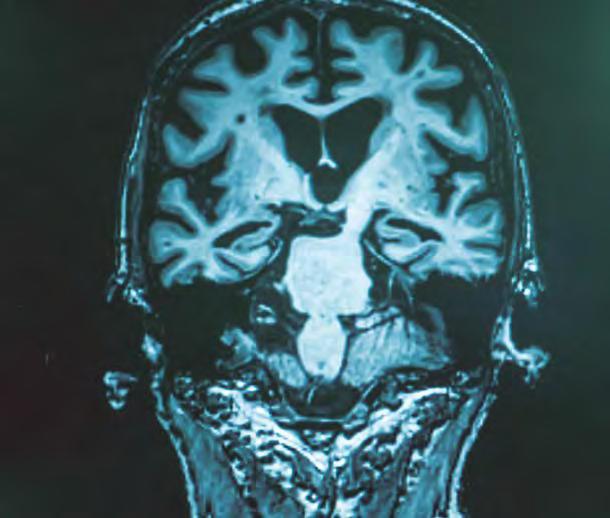

Odontología y Neurología

Asociación entre la periodontitis y las enfermedades

neurológicas y demencias